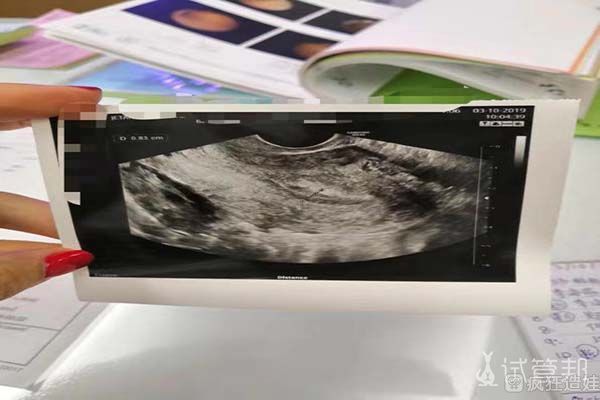

最后成功获取了23颗卵子,并配成了15颗受精卵。经过了5、6天的培养后,进行了基因筛查,有6颗是女胚胎。移植过程很简单,也很快。移植结束后我在医院休息了两个多小时,就回了宾馆。在宾馆呆了三天,才回国。

在移植之后我开始补叶酸、维生素、吃新鲜水果蔬菜喝豆浆。让自己身体和精神上更加舒服放松一些,宝宝可能更容易着床,有时候幸福就是这么不期而至!第十天验孕HCG:232.86验孕成功!